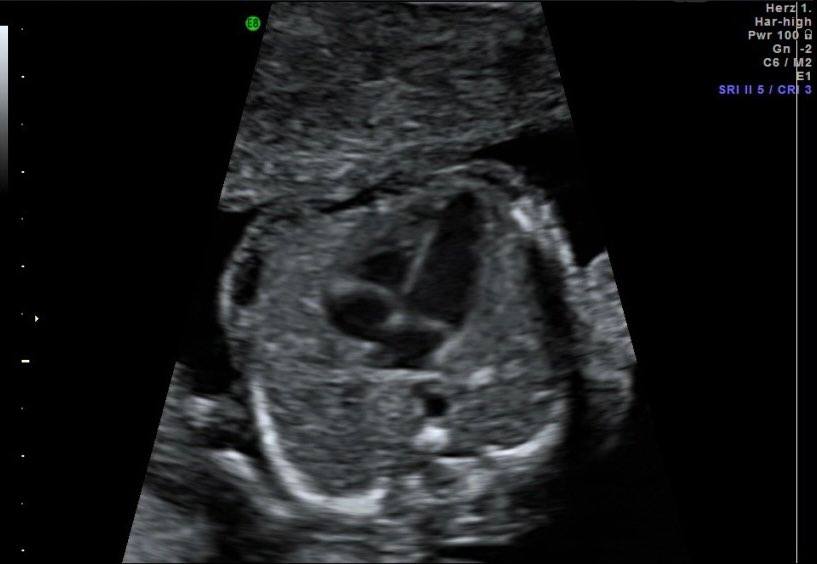

Fetalna ehokardiografija je dijagnostička neinvazivna metoda koja se izvodi od 22-25 gestacijske nedjelje da bi se provjerio položaj,veličina,struktura i ritam fetalnog srca.

Cilj fetalne ehokardiografije je prenatalna dijagnoza urođenih srčanih mana.

Ultrazvučni pregled fetalnog srca je najbolje uraditi između 22-25 gestacijske nedjelje.Pregled traje otprilike 30 minuta.